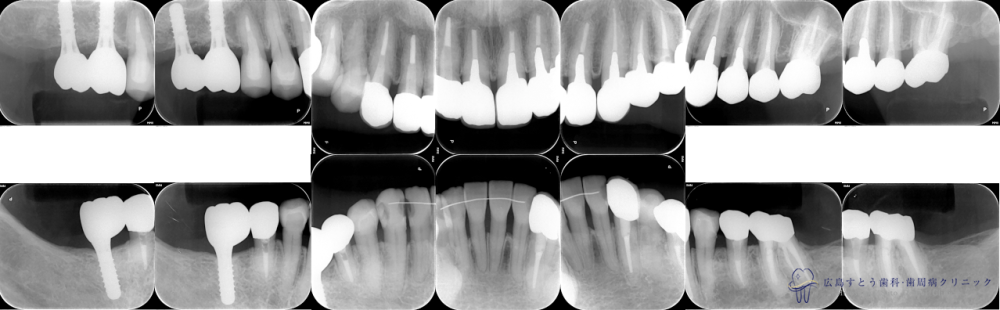

Case1

Before

初診時の状態

初診時の状態

After

メンテナンス開始時

メンテナンス開始時

術前

初診時の状態:矢印の歯は予後不良のため抜歯になりました

右上の抜歯後の状態:歯肉が陥凹してしまっています

治療終了後のレントゲン写真

| 治療名 | GBR(骨再生誘導療法)、インプラント治療(3本分) |

|---|---|

| 治療説明 | 右上と右下の奥歯に歯茎の腫れがあり、診査の結果、歯根破折および重度歯周炎により抜歯することになりました。抜歯後はインプラント治療を希望されたため、抜歯後、失われた歯槽骨を造成するためにGBRを行い、インプラント治療を行いました。 |

| 治療回数・期間 | 約36ヶ月 (歯周基本治療、抜歯、GBR、インプラント治療、矯正治療、補綴治療、ホワイトニング含む) |

| 副作用とリスク | 歯周外科後には一時的に術後に腫れや仏痛や出血が発現することがあります。 治癒の状態によって治療期間が長くかかる場合があります。 |

| 料金 | 155.9万円 (ただしGBR、インプラント治療の部分のみ。他の被せ物や矯正治療、ホワイトニングは別途費用がかかります。) |